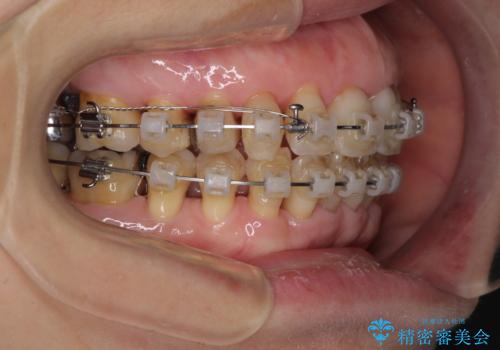

- 矯正装置

- クリアブラケット

近医での歯周病治療の影響でブラックトライアングルが発現していたため、IPR(歯と歯の間を削る)で隙間を改善しつつ、インプラントを固定源に歯列全体を後方へ移動させることとしました。

インプラントは矯正治療では動かすことができないため、インプラント治療を行う前に矯正治療を行う意思があるのかを確認します。